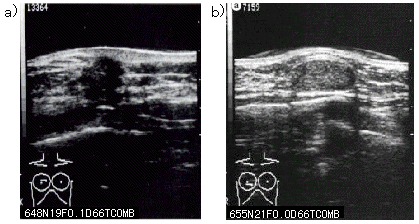

彼らは超音波を使用して、治療前と研究中に50人の嚢胞のサイズと数を測定しました。プロゲステロンゲル治療中に嚢胞の数とサイズが減少し、それを使用した人は痛みの軽減を報告しました。ただし、この治療法が安全で効果的であるかどうかを判断するには、さらなる研究が必要です。

場合によっては、しこりが通常より硬く感じられる場合や、医師ががんなどの別の疾患を除外するためにさらなる検査を提案する場合があります。マンモグラフィーまたは乳房超音波検査の結果は、診断を下すのに役立ちます。これらの画像検査により、乳房組織の詳細が明らかになります。